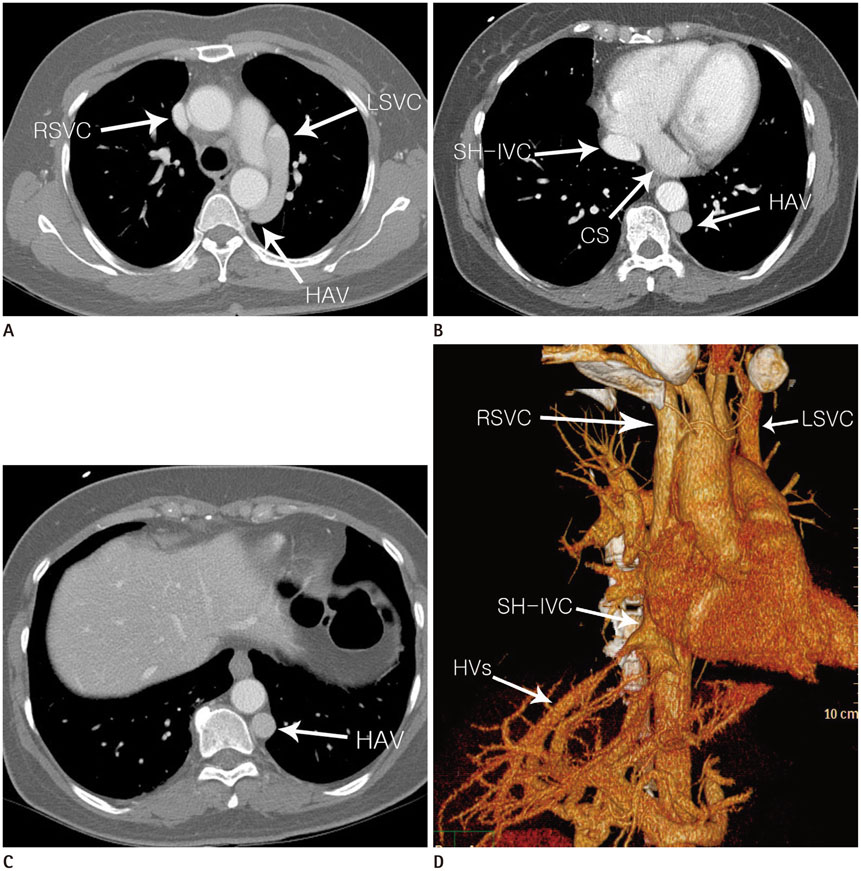

Interrupted Inferior Vena Cava with Hemiazygos Continuation in an Adult with a Persistent Left Superior Vena Cava and Left Single Coronary Artery: A Case Report

A 50-year-old woman was referred to our institution for medical screening due to an incidental finding on abdominal ultrasonography. She underwent chest, abdomen and cardiac multi-detector computed tomography (MDCT). Her MDCT revealed absence of the hepatic segment of the inferior vena cava (IVC), with hemiazygos continuation and a left single coronary artery. The dilated hemiazygos vein drained directly into the persistent left superior vena cava (SVC). Herein, we reported a very rare case combining an incidentally found interrupted IVC with hemiazygos vein continuation, persistent left SVC and a left single coronary artery diagnosed by MDCT.